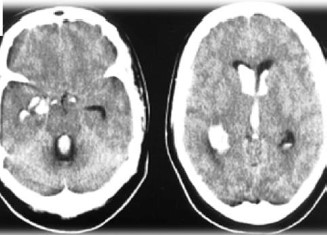

Paciente feminina, 60 anos, levada ao PS por cefaleia súbita, seguida de sonolência, confusão mental e hemiplegia esquerda. A Tomografia foi realizada e apresentou os seguintes achados:

Sobre o caso descrito, assinale a alternativa CORRETA: